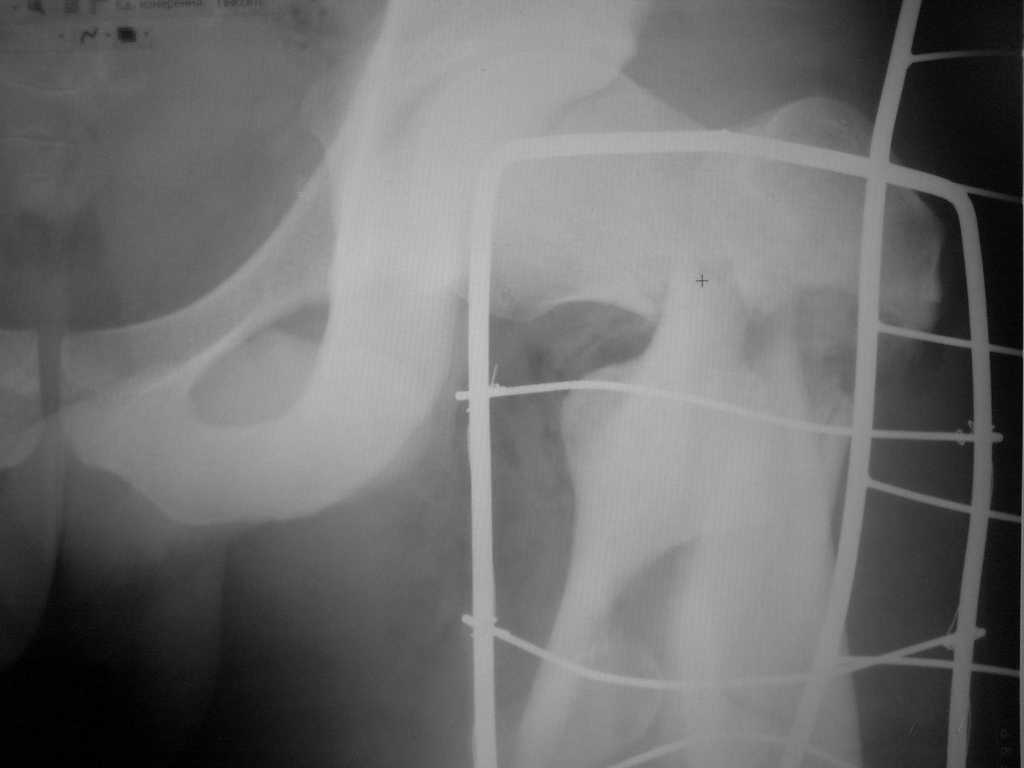

Re: оскольчатый чрезвертельный перелом

А что тут заставляет сомневаться? Здесь настолько очевидно предпочтителен закрытый интрамедуллярный остеосинтез реконструкционным стержнем (проксимальные гвозди толстоваты для такого молодого возраста), что закрадывается мысь о каком-то подвохе.

Уже ставшие традиционными вопроосы - что доступно на месте и каковы собственные намерения?

Желательно бы и снимок бедра на протяжении и в другой проекции.

Не солидно экономить на пленке, это не делает чести презентации. Такие ограниченные нестандартные снимки приводят к тактическим ошибкам.

Предугадать распространение линий перелома при чрезвертельных и оскольчатых переломах трудно, поэтому для принятия правильного решения рекомендуется Компьютерно Томографические исследование.

При отсутствии КТ, снимок на вытяжении поможет увидеть общую картину расположения отломков, особенно потенциальные места введения импланта. Риск раскола в этом случае огромный, поэтому больной должен быть дообследован.

А так для лечения оскольчатых переломов подходят все методы, включая интра- и экстрамедуллярные в зависимости от опыта и наличия импланта.